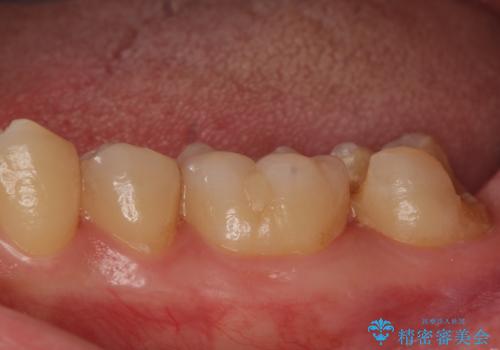

- 他院で入れたセラミックの詰め物が取れてしまい来院。

適合を確認したところ、不適合だったため新しく形を作り直して、型取りをした方が良いことを説明した。

セラミックの詰め物で治療すると、詰め物の範囲が大きくなり、割れてしまう可能性があるので以下の治療の提案をした。

②ジルコニアクラウンによる治療

白い被せ物を被せることで審美的に綺麗になり、割れるリスクが少ないが歯質を多く削ることになる。